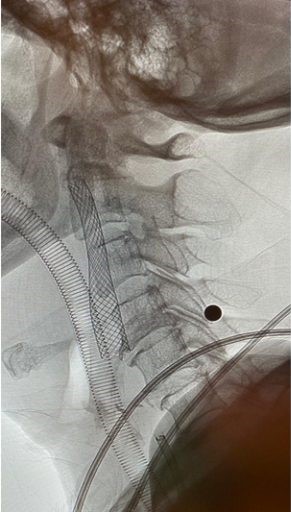

羅先生被送往私家醫院的第一步是進行緊急磁力共振造影,報告顯示羅先生右邊頸和腦部血管大動脈全部都被血栓堵塞着,右邊大腦缺血水腫,導致左邊手腳冇力和神智半昏迷。經過腦血管外科醫生的診斷和急救,在全身麻醉下,醫生使用尤如髪絲微細的導管,經過病人右邊大腿的腹股溝的大動脈而入,導管再經過腹部和胸腔的大動脈一直向上,遊走到病人右邊的頸和腦部血管大動脈,進行機械式血栓吸取內血管治療急救。

手術成功 患者手腳活動能力恢復

經過1小時的血管急救,所有血栓都被移除,羅先生的右頸和腦部血管都給順利打通,腦部缺血情況立即得到改善。血栓被吸取後,腦血管外科醫生發現羅先生的右頸內動脈有嚴重血管狹窄的情況,這個狹窄就是羅先生中風的主要原因。醫生因此植入血管支架來重新擴張狹窄的血管,以防止羅先生將來中風復發。全身麻醉清醒後,羅先生的大腦意識和手腳活動能力即時好轉,他其後再被送回另一間公立醫院繼續康復治療。